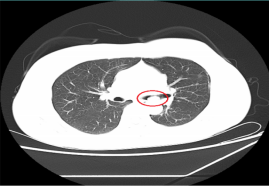

近日,在胸心外科艾成博士的主刀下,我院顺利完成全区首例单孔胸腔镜右肺下叶切除手术,标志着我院胸心外科胸腔镜微创技术达到了区域领先水平。 患者是一名中年女性,半年前因右侧支气管内新生物,出现反复咳嗽、咯血等症状,辗转多家医院,开展多次治疗,都没有明显好转。2周前病情加重,管腔内新生物完全堵塞支气管,便前往我院胸心外科治疗。 对于绝大部分肺恶性肿瘤及部分肺良性疾病患者来说,最常见的治疗方式是开展肺叶切除手术。近年来,胸腔镜肺叶切除术迅速发展,逐渐取代了传统的“开胸切肺”,然而当前国内开展该技术仍以三孔或者四孔法为主。 “实际上,该手术可以只通过一个单孔完成全部操作,即术中胸腔镜和操作器械均从一个孔进出,完成肺叶切除全部流程。”艾成介绍,单孔胸腔镜下肺叶切除手术对患者的损伤更小,切口更加美观,术后疼痛更轻、恢复得也更快。 在手术麻醉科的紧密配合下,手术顺利实施。通过胸壁一处长约4cm微创切口,成功完成肺叶切除,手术用时仅两小时,患者即拔管返回病房。